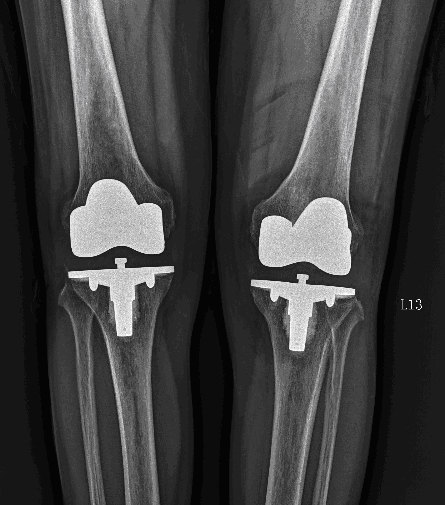

人工膝盖

人工膝关节置换中老年人膝盖疼痛的终极治疗方法

丰县宋楼70岁老李徐州二院骨科人工膝关节置换手术过程照片